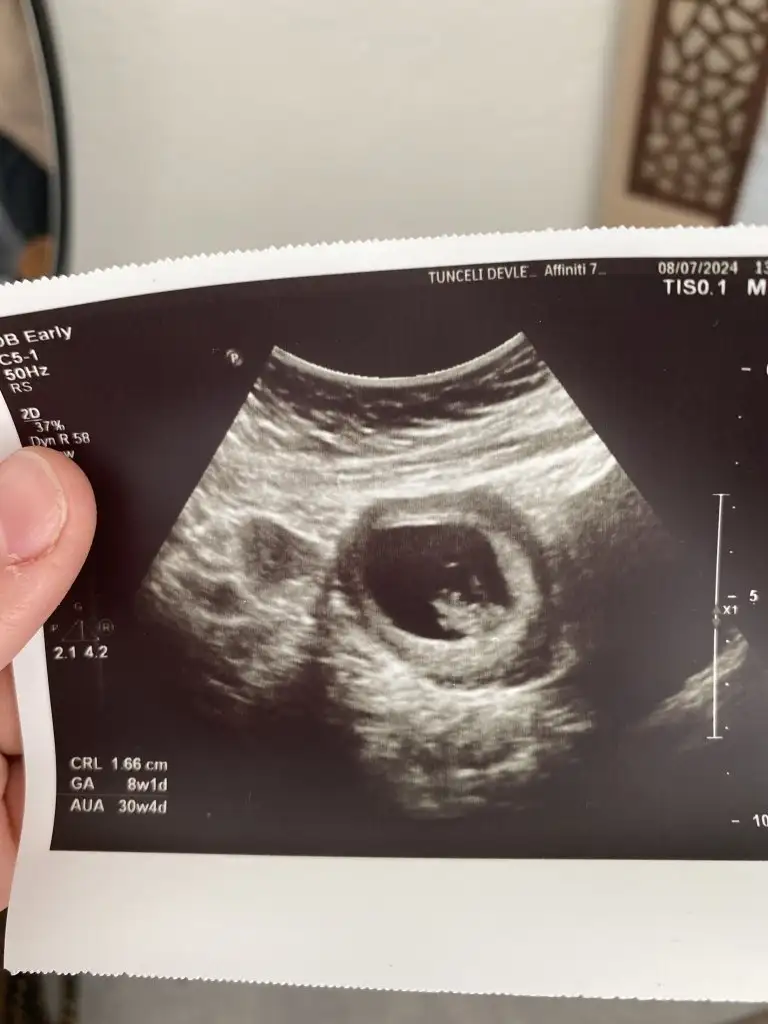

9 hafta 1 günlük cinsiyet tahmini yapar misiniz

• 20240729_124608.webp

20240729_124608.webp

17,4 KB · Görüntüleme: 62

• 20240729_124559.webp

20240729_124559.webp

12,5 KB · Görüntüleme: 64